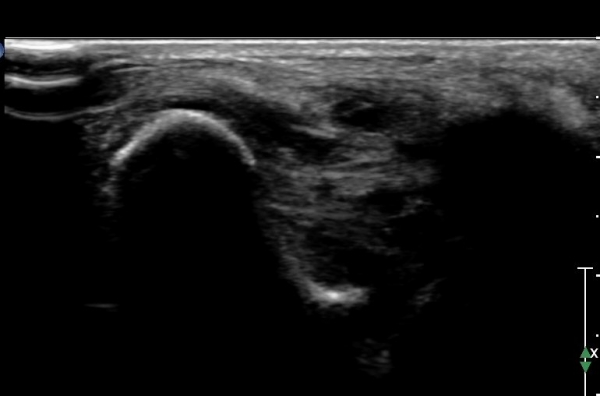

Àü°ÅºñÀδë ÇϺΠÁ¾´Ü¸é°Ë»ç¿¡¼­ Àü°ÅºñÀδëÀÇ Àú¿¡ÄÚ À§Ãø°ú Á·±Ùµ¿ÀÇ ¼ö¾×Àú·ù°¡

°üÂûµÈ´Ù(»çÁø 2, 3, 4).